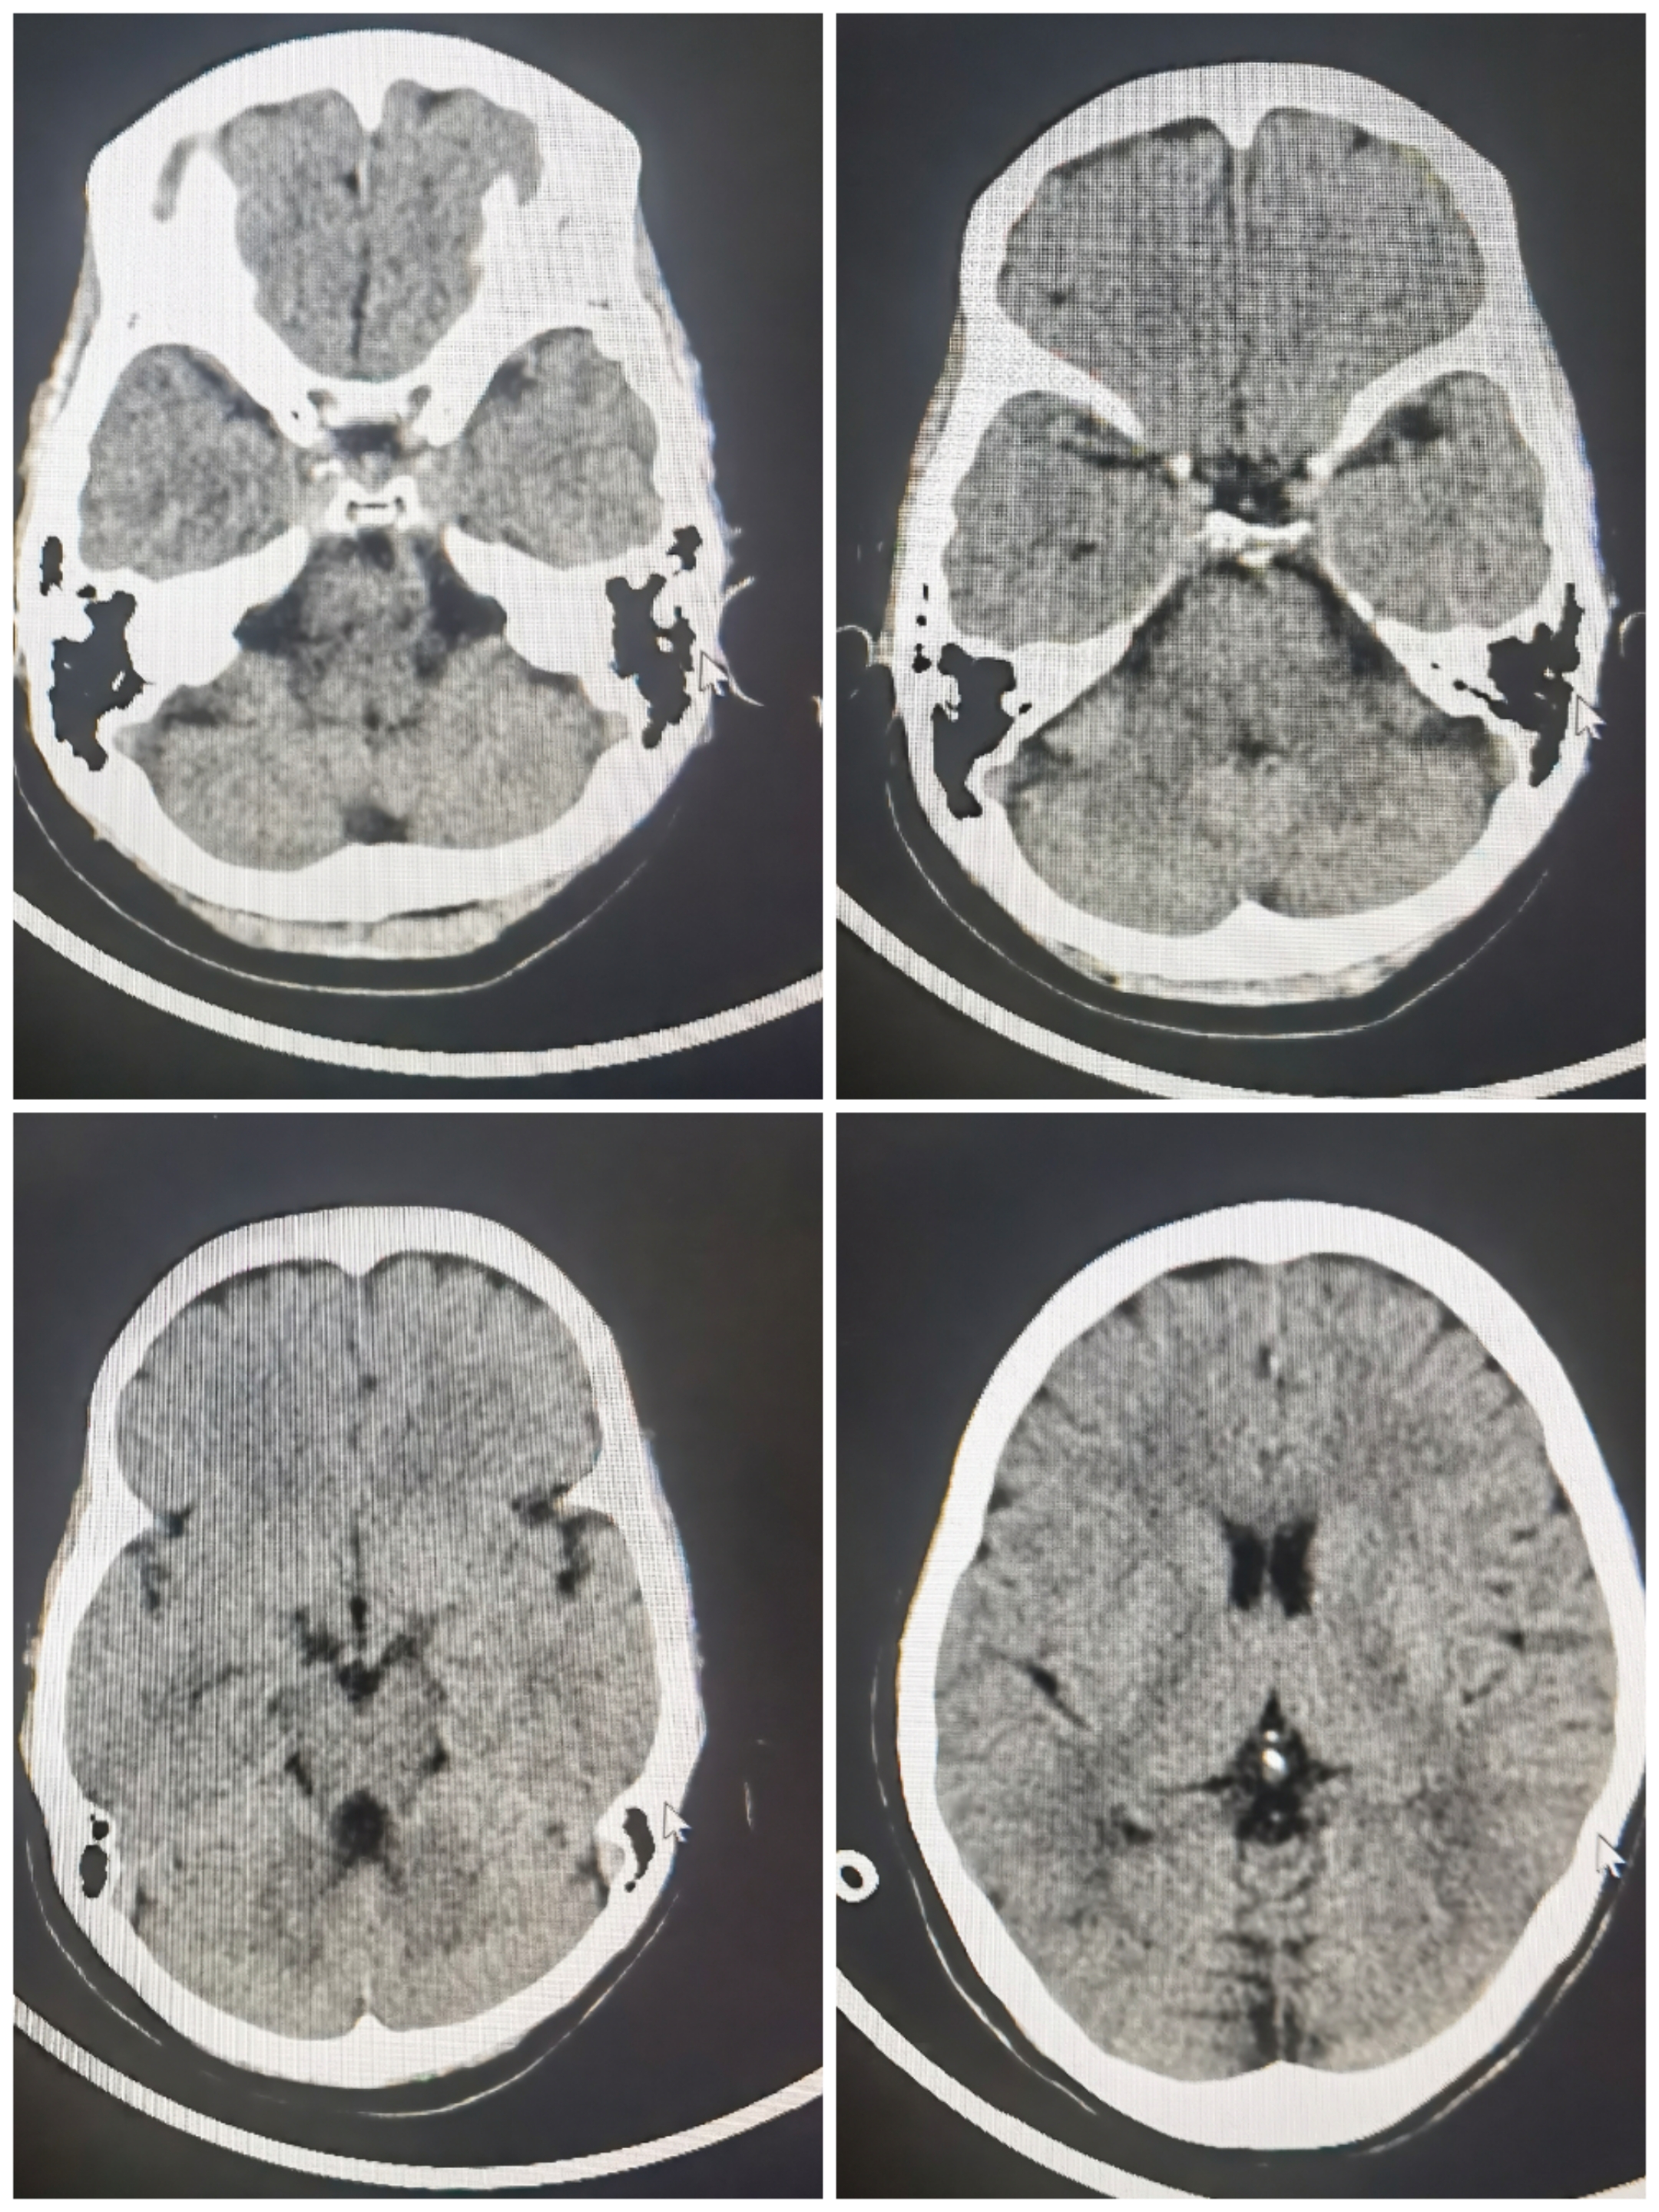

病例2大脑中分叉分叶动脉瘤

SAH入院,Hunt-Hess分级2级,

术前CTA:右侧大脑中分叉部动脉瘤

术前造影3D重建

术前计划:支架导管释放至上干,应用开环支架穹窿效应保护下干,双微导管分区栓塞

拟支架释放角度

栓塞过程

栓塞术后情况

栓塞术后3D重建